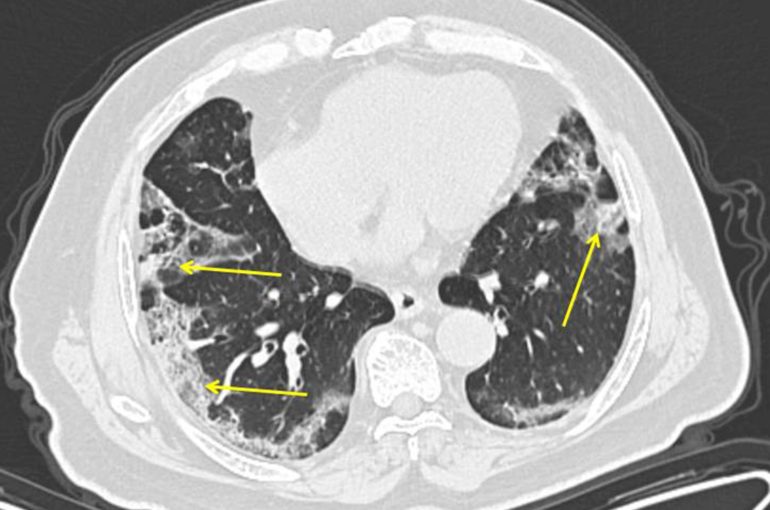

Na nedatovanej snímke je CT pľúc 65-ročného pacienta z Číny, ktorý má ochorenie COVID-19. Zápaľ plúc spôsobený novým koronavírusom je viditeľní ako výrazná hmlistá škvrna na vonkajších okrajoch pľúc označená šípkami. Foto: TASR/AP